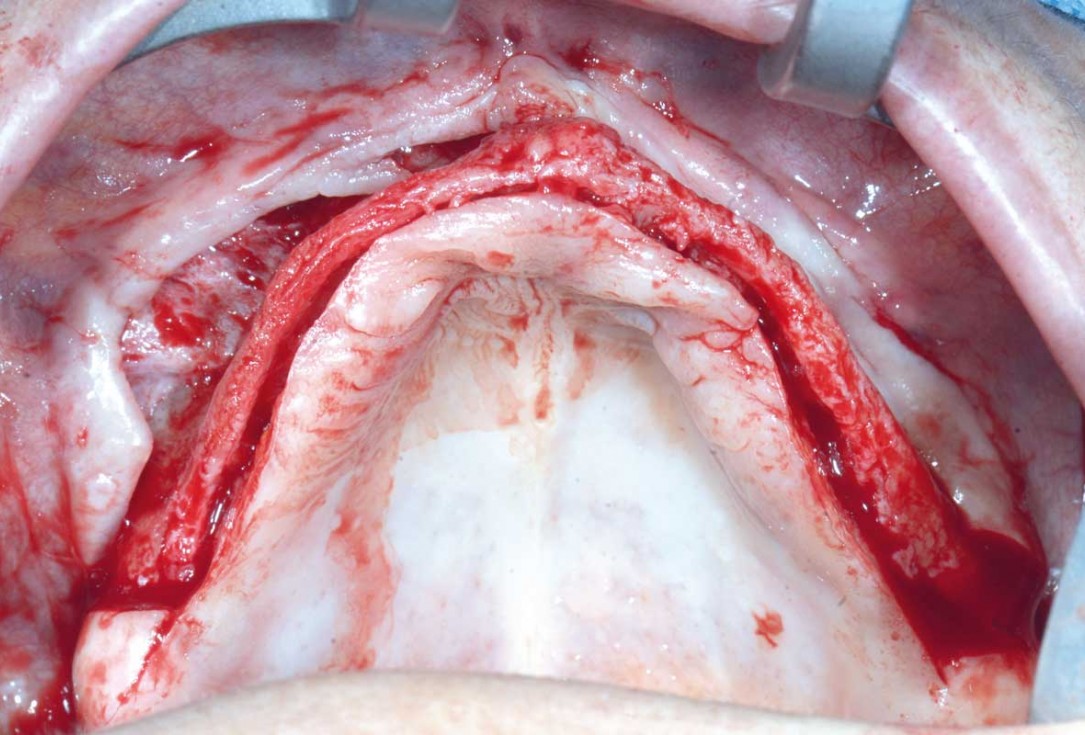

Full arch GBR using cerabone®, maxgraft® and Jason® membrane with simultaneous implantation of 6 Straumann® implants - Dres. A. Signorio and G. Molina